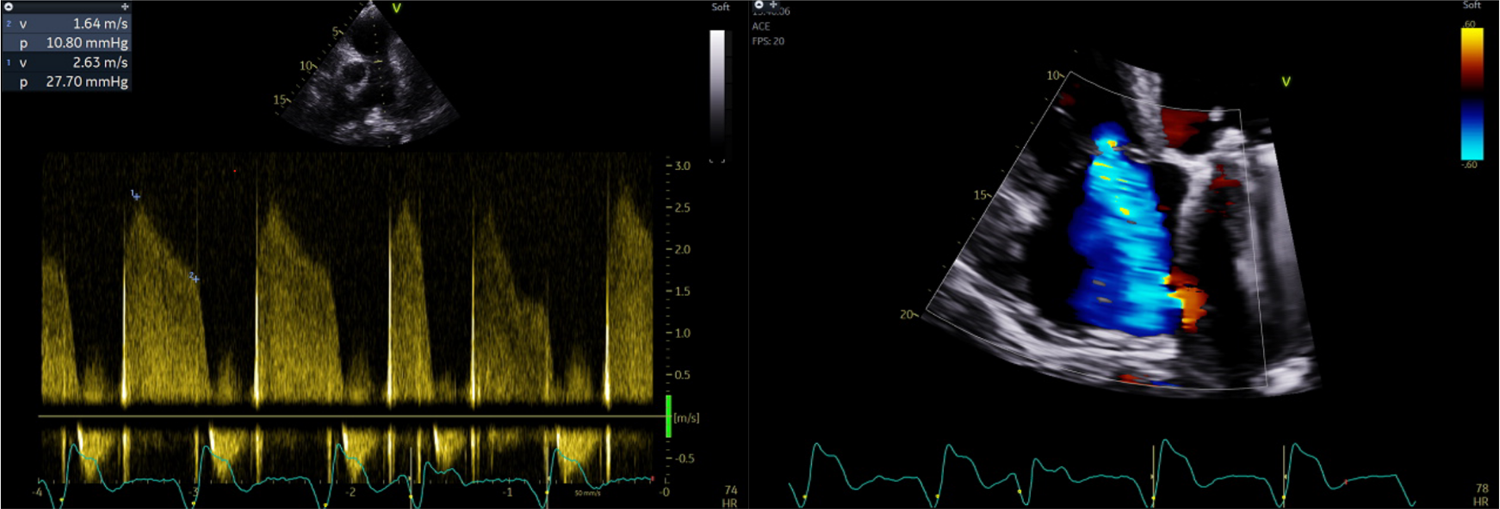

Image of the Week - 25 October 2023

Doctor Bharath Raj Kidambi

Doctor Vikas Purohit

Doctor Sriram Veeraraghavan